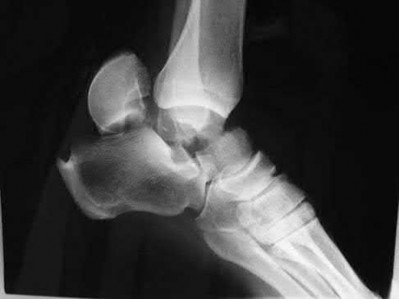

A 25-year-old female is involved in a motor vehicle collision. She presents with the isolated injury seen in Figures A through D. Her leg is swollen but her skin is intact. She has no clinical signs of compartment syndrome. Which of the following treatment options will allow for maintenance of fracture alignment and minimize the risk of soft tissue complications?

The patient presents with a closed distal third metaphyseal-diaphyseal distal tibia fracture with simple intra-articular extension. Immediate intramedullary nailing along with percutaneous fixation of the articular component provides appropriate restoration of length, rotation and alignment and minimizes the risk of wound complication.

Displaced distal third tibia fractures may be associated with simple intraarticular extension. Operative treatment of intra-articular distal tibia fractures has historically been performed with open reduction and internal fixation. Early open reduction and plate fixation of pilon fractures has been associated with high rates of infection and wound complication. In select patterns with simple articular extension, percutaneous screw fixation and medullary nailing may provide appropriate reduction with minimal soft-tissue risk.

Figures A and B demonstrate a distal third tibial shaft fracture with simple intra-articular extension. The axial and coronal CT cuts in Figures C and D further clarify the articular injury. Illustrations A and B demonstrate a comminuted distal third tibial fracture with simple intra-articular extension. Illustrations C and D are fluoroscopic images of the same injury after intramedullary nailing and percutaneous fixation of the articular component.